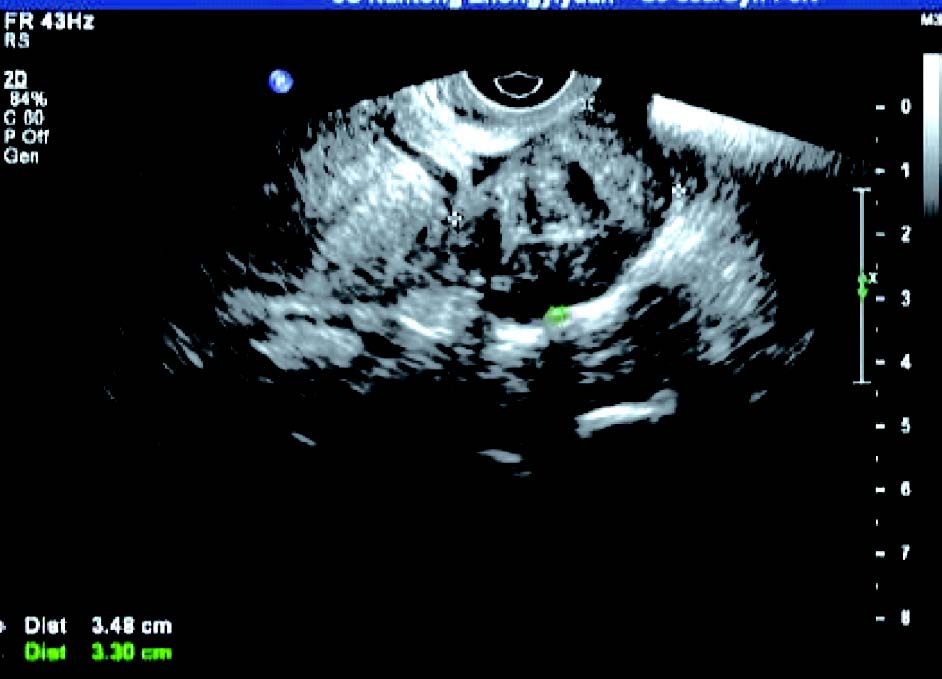

患者,女,42岁,常规体检。超声检查声像图显示:子宫前位,三径正常,边界清,子宫内膜欠清。肌内可见多个低回声包块,较大者约1.7cm×1.4cm(前壁)、1.8cm×1.4cm(前壁)、1.9cm×1.4cm(后壁),边界清,有假包膜,内部回声均匀,子宫边界规整。CDFI探查:较大团块周围见半环状彩色血流信号。包块内未见彩色血流信号。宫腔内可见节育器影像,距宫底约1.5cm。

超声提示:子宫肌瘤(肌间);宫内节育器,位置正常。